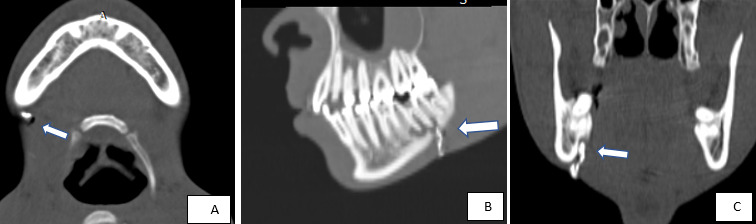

To further delineate the tract, CT-guided percutaneous fistulography was performed. A fine catheter was carefully introduced through the external skin opening, and approximately 1.5 cc of water-soluble iodinated contrast medium was slowly injected. The procedure demonstrated a well-defined, hyperdense, contrast-filled sinus tract measuring approximately 3 cm in length, extending from the cutaneous surface to a periapical abscess associated with the affected molar (Figure 3). These radiologic findings confirmed the diagnosis of an odontogenic cutaneous fistula

As demonstrated in our case, iso-volumetric, high-resolution datasets obtained during contrast-enhanced CT scanning—combined with post-processed multiplanar reconstructions (axial, sagittal, and coronal) and advanced imaging techniques such as volume rendering (Figures 2–4) and maximum intensity projection—enable comprehensive mapping of the sinus tract. This approach allows for accurate identification of the tract’s type, length, internal origin, and any associated complications, such as bone erosion or abscess formation.14,15